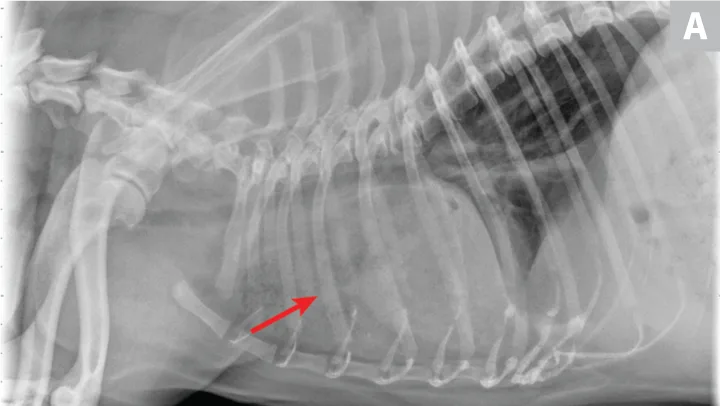

Dogs with bacterial pneumonia are typically presented with acute-onset coughing, lethargy, inappetence, and/or respiratory distress. An inflammatory leukogram and pyrexia, although common, are not always present. Radiographs may reveal an interstitial-to-alveolar pattern with a cranioventral distribution (Figure 1). Atypical distributions can also occur.5

FIGURE 1

(A) Bronchopneumonia. Cranioventral distribution of alveolar disease with air bronchograms. (B) A patchy distribution can be observed on the lateral projection. The changes overlying the heart may be missed in subtle cases.